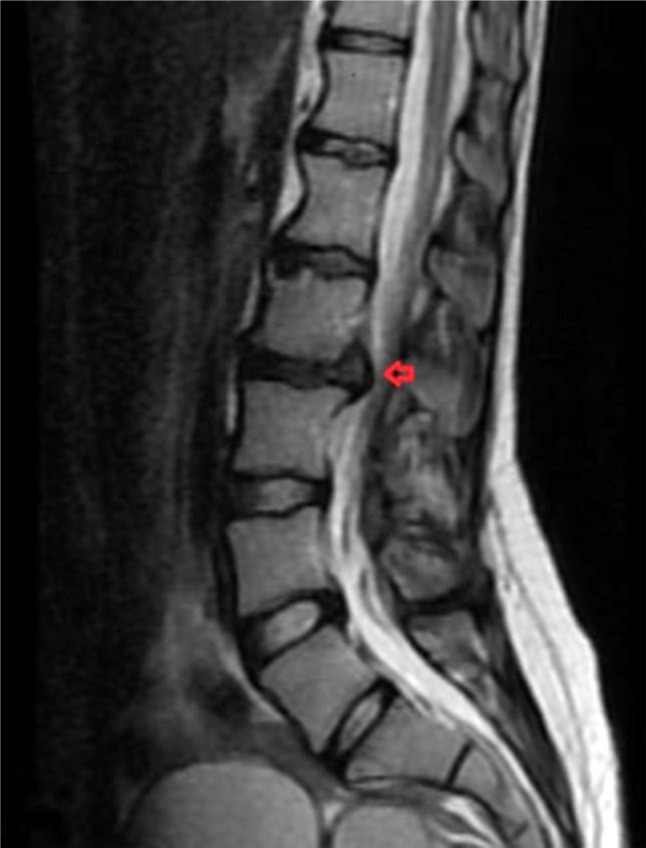

横贯脊髓炎是一种罕见的疾病,以脊髓炎症为特征。这些表现可能与原发性运动神经元损伤有关,也可能与非特异性表现有关,如四肢肌肉力量和感觉丧失。在此,我们报告了一名21岁的女性横脊髓炎患者,主诉为肌肉无力和尿失禁,经腰椎成像诊断为腰椎间盘突出,手术后症状没有改善。

Transverse myelitis is a rare disease characterized by inflammation of the spinal cord. These findings may present with findings related to primary motor neuron damage or with nonspecific findings, such as loss of muscle strength and sensation in the extremities. Herein, we presented a 21-year-old female patient with transverse myelitis with complaints of muscle weakness and urinary incontinence who was diagnosed with lumbar disc herniation after lumbar imaging and whose complaints did not improve after surgery.